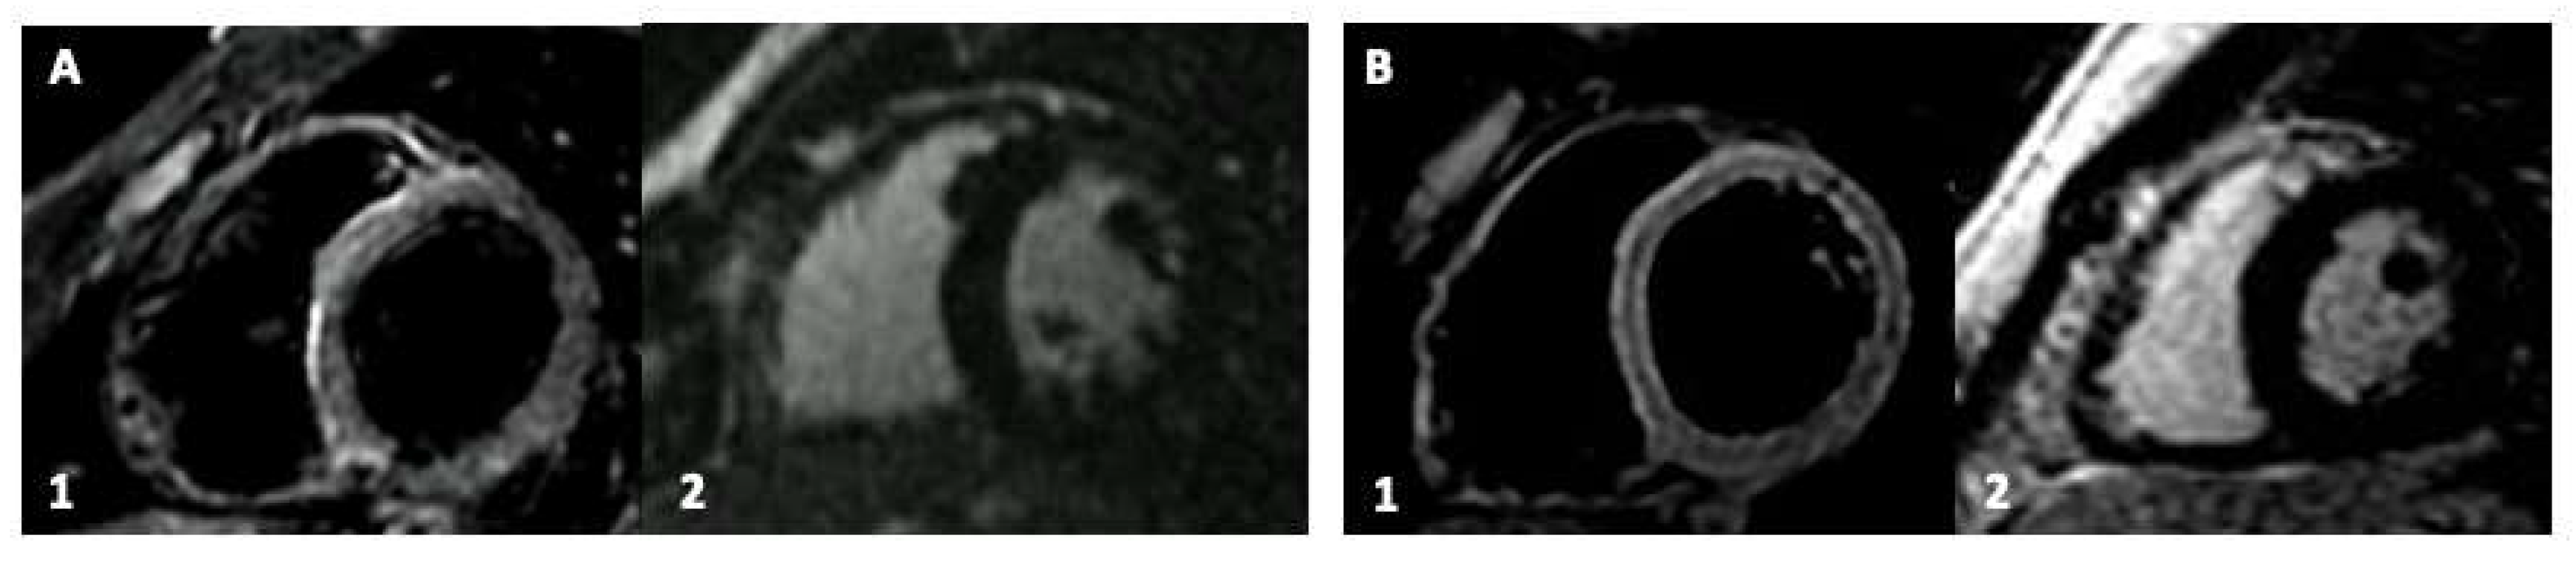

After a median follow-up time of 3.0 ± 0.5 months, all the patients are alive and asymptomatic. The CMRs performed after the ibuprofen and colchicine treatment did not present persistent cardiac involvement (Figure 2). No CRP or Hs-TnI elevation was found. The patient that experienced atrial tachycardia was acutely and effectively treated with metoprolol and did not show further arrhythmias at the 24 h ECG Holter-monitoring, suggesting a self-resolution.

Figure 2.

Cardiac magnetic resonance (CMR) imaging at the follow-up after medical treatment of young patients with vaccine-related myocardial involvement. Panel (A,B): Participants with previous inferolateral myocardial involvement. Sub-Panel 1, Short-Tau Inversion Recovery (STIR) images for myocardial edema detection. Sub-Panel 2, late gadolinium enhancement (LGE) images.